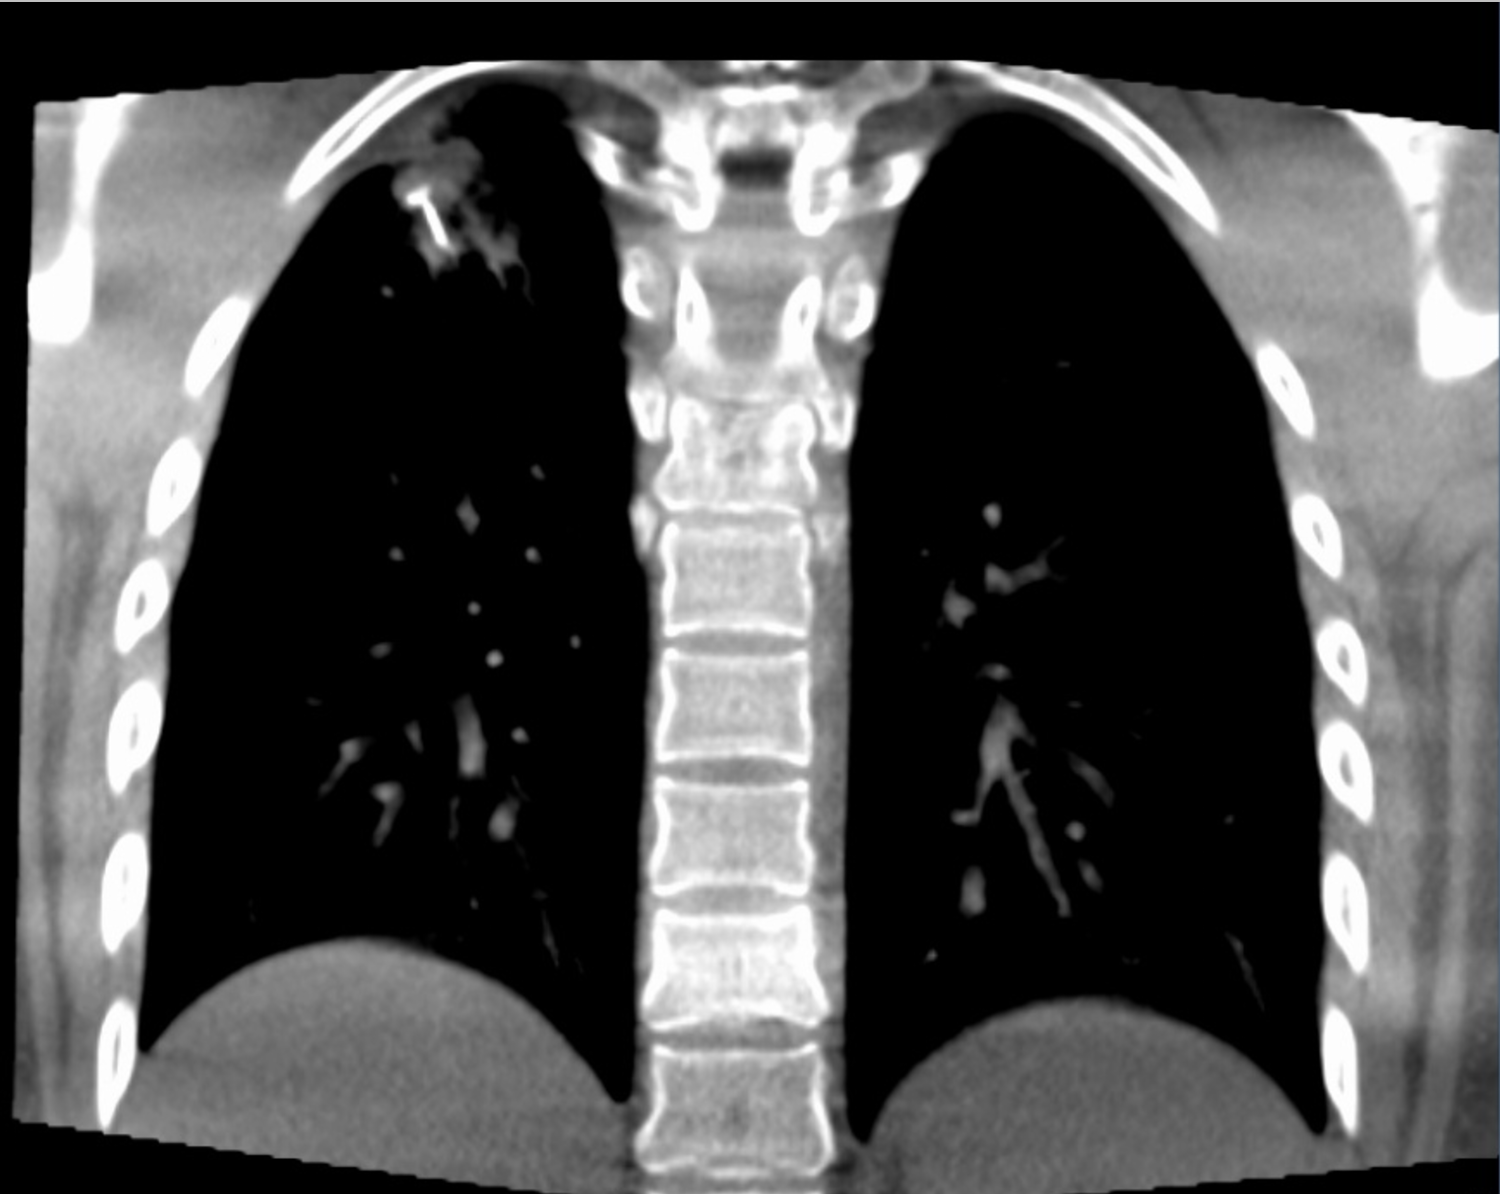

A young asymptomatic woman was referred after an incidental right upper lobe pulmonary nodule was discovered during routine screening. CT thorax revealed a 17 × 15 mm subpleural nodule with lobulated margins and focal calcification, raising suspicion for a tubercular granuloma in this healthcare worker from a tuberculosis-endemic region.

CT Axial

CT Coronal

Advanced bronchoscopy was performed using augmented fluoroscopy with cone beam CT (CBCT) confirmation of tool-in-lesion, followed by transbronchial cryobiopsy with a 1.1 mm cryoprobe. The procedure was uneventful.

Histopathology demonstrated features consistent with a benign pulmonary hamartoma, while microbiological testing including GeneXpert, AFB smear, fungal smear, and bacterial cultures was negative.

This case highlights that pulmonary hamartomas can radiologically mimic tubercular granulomas. It also underscores the value of CBCT-guided bronchoscopic navigation and cryobiopsy in safely obtaining diagnostic tissue from peripheral pulmonary lesions, helping avoid unnecessary anti-tubercular therapy.